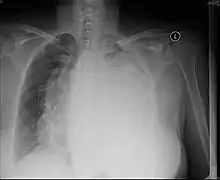

Pulmonary hypoplasia

Fetal conditions can also cause mediastinal shift during development. For example, pulmonary hypoplasia is the underevelopment of a lung due to various etiologies. These include agenesis due to gene mutation, fetal hydrothorax, and congenital diaphragmatic hernia. These conditions lead to incomplete development lung tissue or hypoplasia. This can be unilateral or bilateral and is seen on x-ray as a mediastinal shift towards the side of the underdeveloped lung.[15][16] Additionally, mediastinal shifts can also be detected using antenatal ultrasonography.[17]

Pectus excavatum

This condition is often referred to as "funnel chest" and is observed as depression of the anterior chest at the xiphisternum. Pectus excavatum is commonly unilateral and therefore can lead to asymmetric distribution of thoracic organs. Therefore, a mediastinal shift can be seen in severe cases. Radiographic features include a leftward deviation of the heart and deformed third to seventh ribs. Patients often present with exercise tolerance, cardiac arrythmias, and heart murmur.[18]